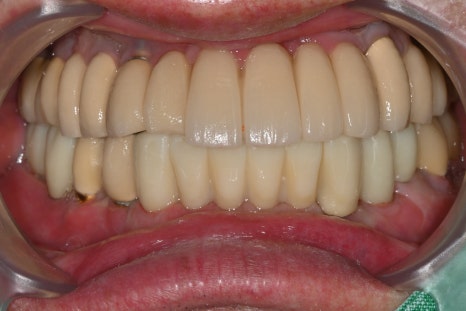

치료 후: 최종 보철물 완성 후 엑스레이, 정면·측면 사진

왼쪽 사진: 완성된 보철물의 정면 모습입니다. 심미성과 기능 모두 만족스럽게 회복되었습니다.

오른쪽 사진: 측면에서도 자연스러운 곡선과 교합이 잘 유지되어, 편안한 저작이 가능한 상태입니다.